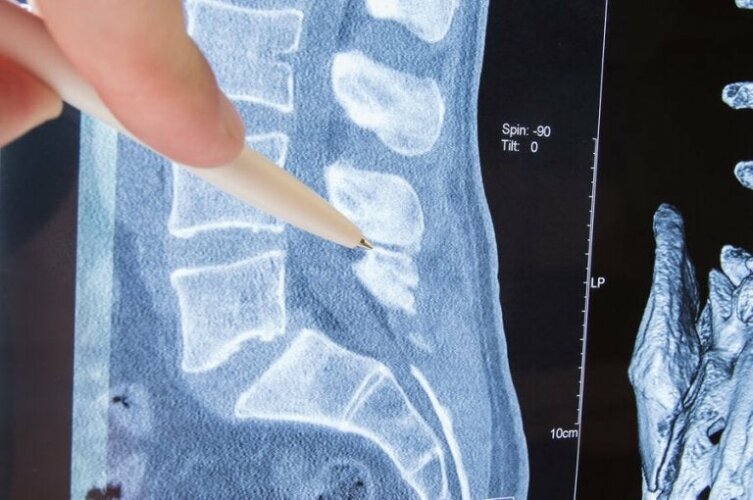

Η σπονδυλική στήλη είναι μια οστική δομή σχηματισμένη από σπονδύλους οι οποίοι προστατεύουν τα οστά και σας επιτρέπουν να κινείστε ελεύθερα. Οι σπόνδυλοι έχουν τρύπες σε κάθε τους πλευρά από τις οποίες τα νεύρα πηγαίνουν σε διάφορα σημεία του σώματος.

Το τμήμα του νεύρου που βγαίνει από τους σπονδύλους ονομάζεται “νευρική ρίζα”. Η ριζοπάθεια είναι η συμπίεση των νεύρων, πιο συγκεκριμένα της νευρικής ρίζας. Τι την προκαλεί; Ποιες είναι οι κλινικές της εκδηλώσεις; Σε αυτό το άρθρο θα δώσουμε απάντηση σε αυτά τα ερωτήματα και θα σας ενημερώσουμε για τις υπάρχουσες θεραπείες.